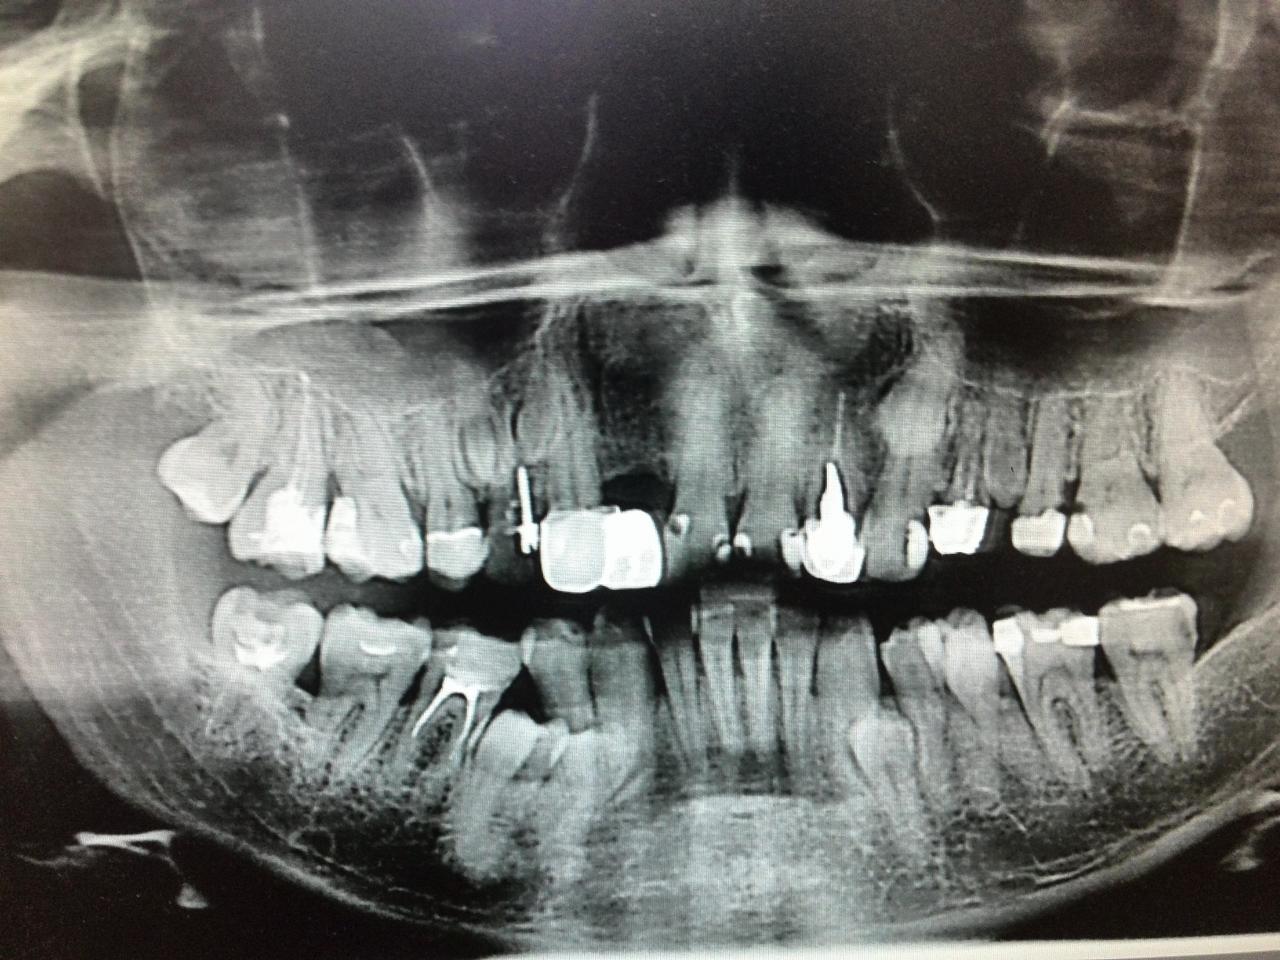

Нажмите на изображение для увеличения

Название: IMG_20140606_161856.jpg

Просмотров: 109

Размер:	160.1 Кб

ID:	8274619

Мало ли, где, сколько и каких зачатков природа "посеяла"...Вот у этого пациента кроме стандартного набора было еще больше 10 сверхкомплектных...в том числе и второй верхний клык слева, лежавший параллельно небу под носом практически как бы от затылка к лицу... Все восьмые зубы удалялись по два раза, вначале "родные", потом сверхкомплектные...под/над корнями уже не первых премоляров видны "букеты" зачатков, очередные решившие прорезаться зубы снимают коронки с ранее прорезавшихся и разрушают их, выдавливают пломбы и разрушают кость. И все б ничего, если бы пациент не обладал еще аллергией на все анестетики и не имел в анамнезе анафилактический шок. "А вы говорите, не бывает" (с)